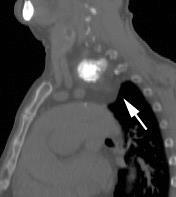

Carcinoma subglótico

Tumor poco frecuente. 1,8% de los tumores laríngeos.

Tendencia a invadir el anillo cricoideo y el esófago.

Ganglios + frecuentes

Mac Neill SD et al. Survival of patients with subglottic squamous cell carcinoma. Curr Oncol. 2018